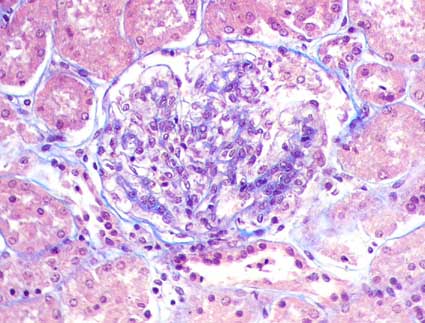

Figura 2.

Mayor grado de proliferación celular mesangial que en la imagen

anterior (H&E, X400).